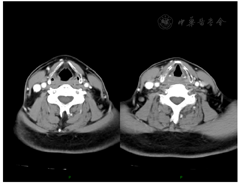

纤维喉镜检查:右侧梨状窝及劈裂环后肿物,下咽部右侧梨状窝可见菜花样肿物(活检),环后区受侵犯,右侧声带活动受限,左侧声带活动正常。(图1)

头颈部增强CT检查:右侧梨状窝处软组织增厚,局部形成肿物,边界不清楚,最厚处约1.4 cm,不均匀明显强化,侵及右侧杓状会厌襞及环后区,与右侧甲状软骨板关系密切。右侧颈中下深组、颈后三角区见数个肿大淋巴结,不均匀强化,大者短径约1.1 cm。余双侧颈深链见多发形态饱满淋巴结,大者短径约0.7 cm。(图2)